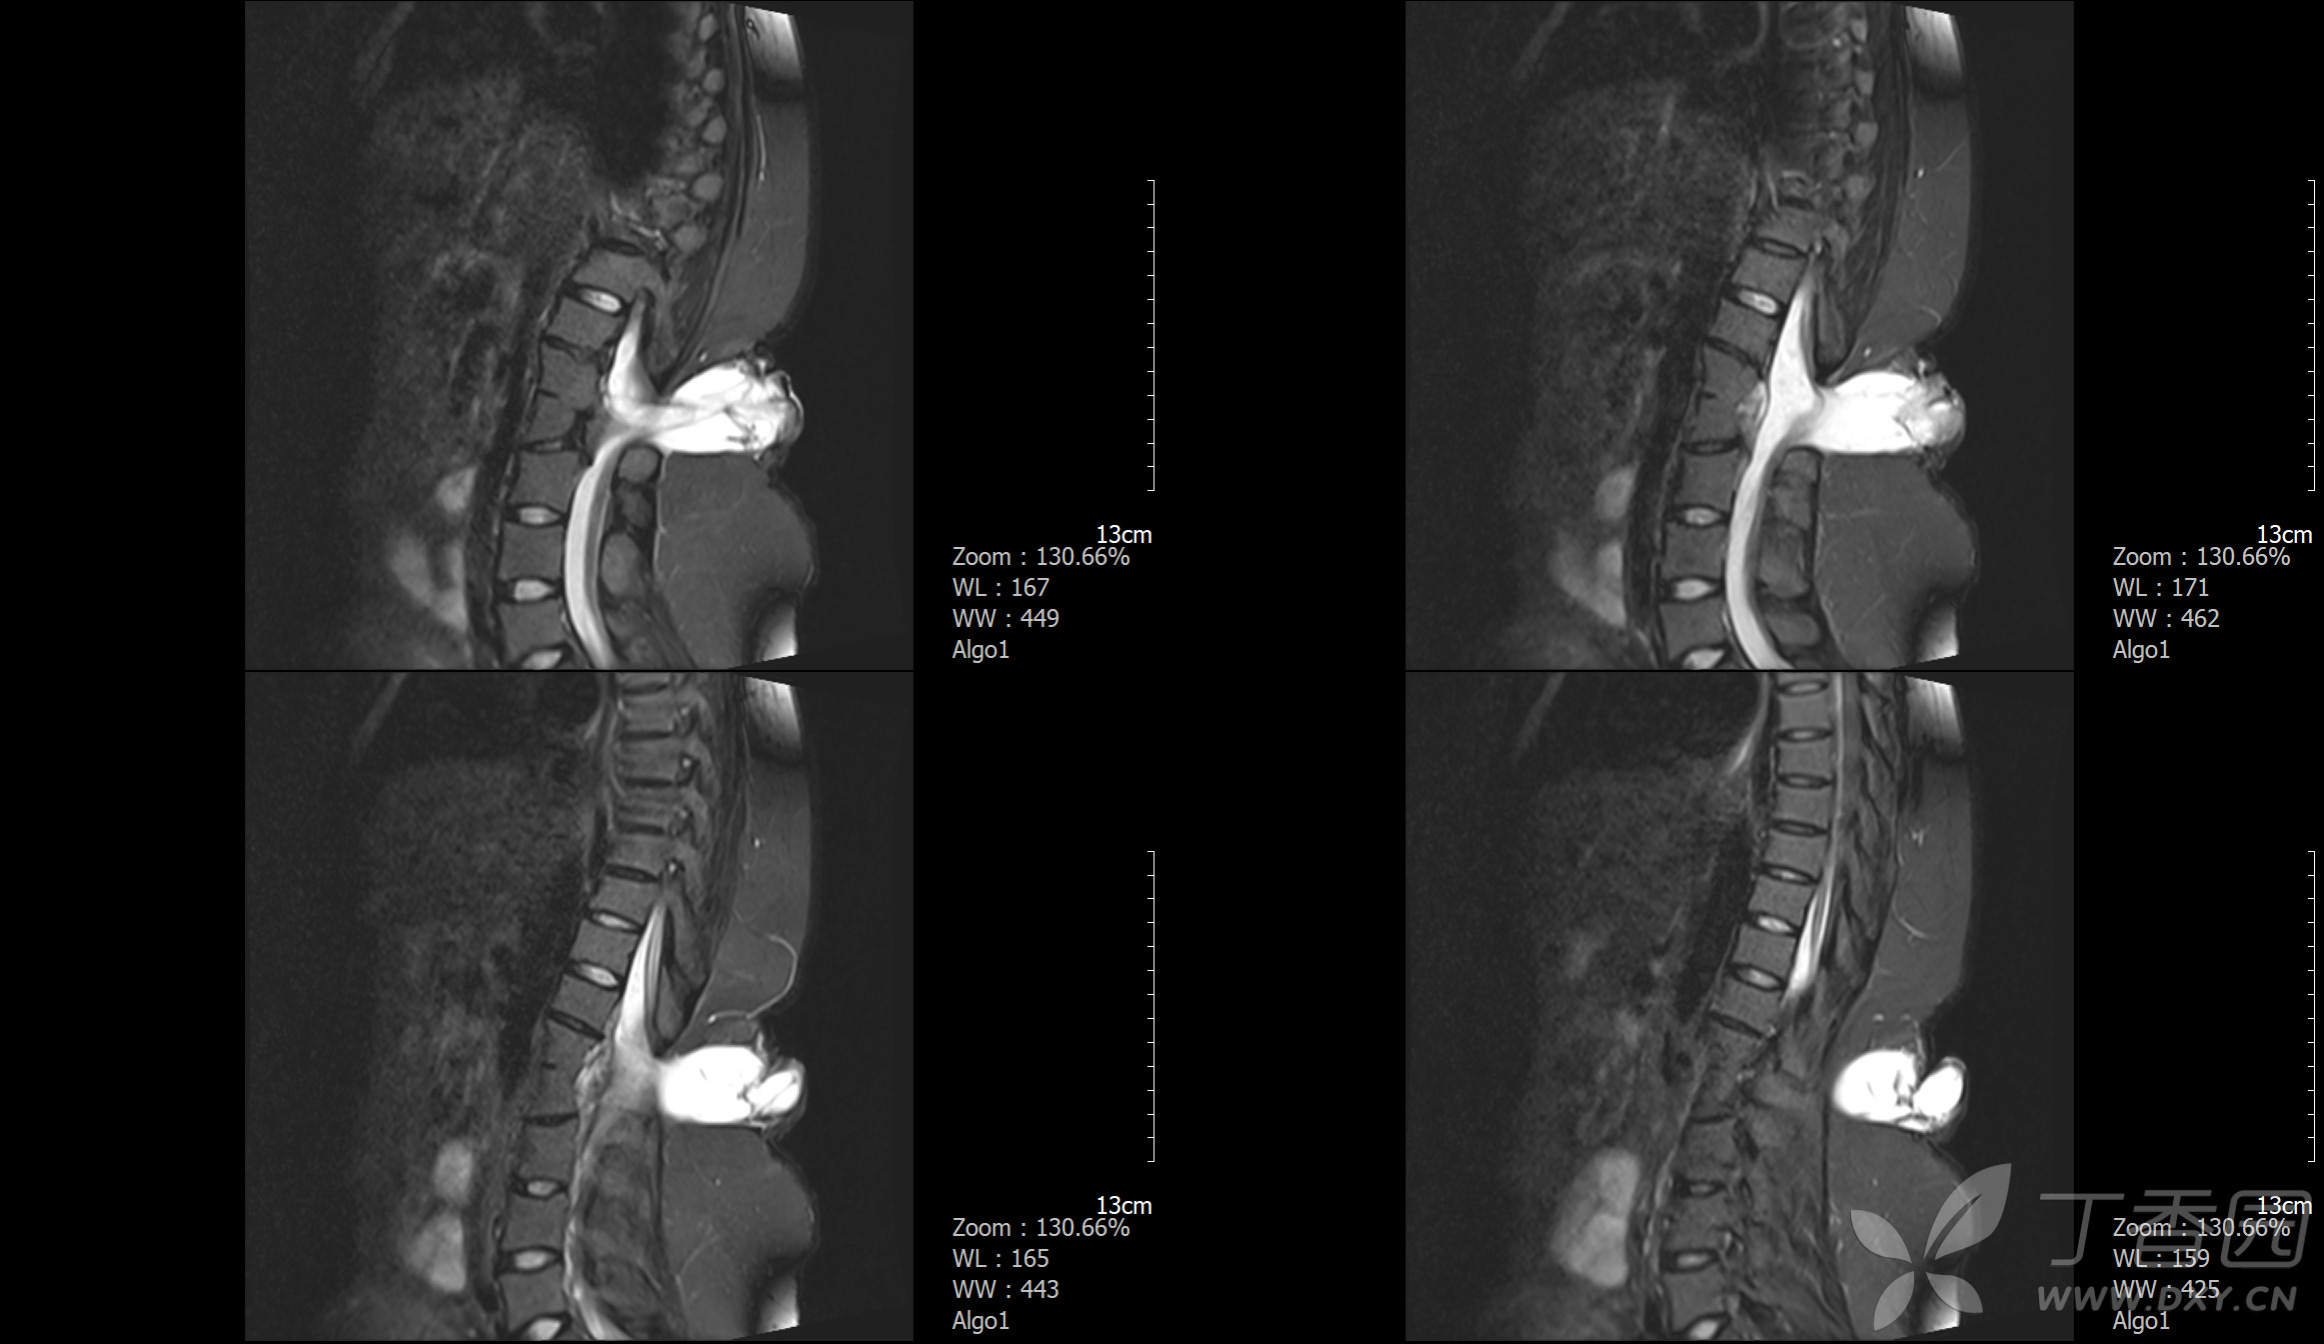

患者24岁,女性

剖宫产后4天。

患者诉自出生时背部就见一包块凸起,一直未就医,此次住院行剖宫产,顺道就医~~~

MRI资料如下: